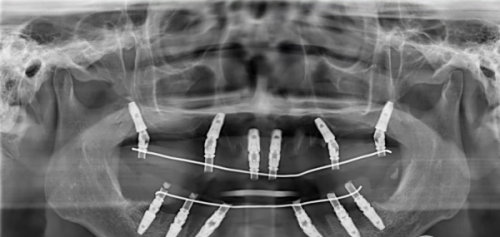

在设备和团队方面,广州曙光口腔医院引进了国内外精良的口腔诊疗设备,如数字化口腔全景机、种植导航系统等,这些设备能够为医生提供更正确的诊断依据,提高治疗的精细度。同时,医院汇聚了一批经验多、技术不错的口腔医生,他们在种植牙、牙齿矫正、牙齿美容等领域都有着深入的研究和丰富的临床经验。